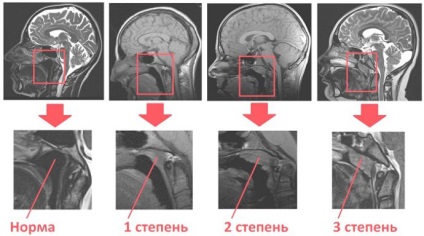

Három fokozata van az adenoid vegetáció, hogy pontosan meghatározzák, hogy szükség van, hogy vizsgálja meg, hogyan néz orrpolip.

Az emelkedés mértéke az orrpolip

- Norma. Enyhe emelkedése orrnyálkahártya párosított formában. Szín - világos rózsaszín, nem különbözik a színe a nyálkahártya.

- Orrpolip 1 fok. Nasopharyngealis mandulában szövetet növeljük olyan mértékben, hogy a nyílás fedi egy harmadik Hoan.

- Adenoides 2 fok. Nasopharyngealis mandulában szövetet növeljük olyan mértékben, hogy a nyitó Joan átfedi kétharmada.

- Adenoides 3 fok. A növekedés olyan méretű, hogy a nyílást lezárjuk choana vegetáció szinte teljesen vagy 100%.